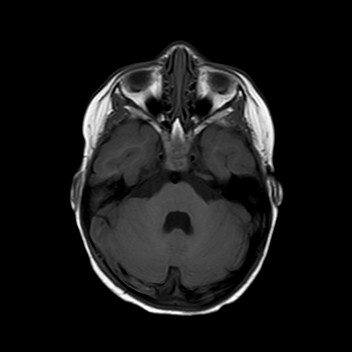

Esegue quindi una TAC che mostra una frattura

dell’osso occipitale con la presenza di un ematoma epidurale

di circa 9 mm adiacente al seno sigmoideo di destra.

La bambina inizia quindi terapia con enoxaparina alla dose di 1700 UI x 2/die con aggiunta di terapia antibiotica con ampicillina-sulbactam per profilassi. Nei giorni successivi Teresa è stata bene, l’instabilità è andata progressivamente scomparendo senza vomito o cefalea. I successivi controlli all’angio-RM e alla TAC hanno mostrato un rallentamento del flusso in seno sigmoideo destro con tumefazione e netta iperdensità dello stesso, che sono andati progressivamente scomparendo con solo una minima falda ematica residua al giorno della dimissione, dieci giorni dopo il trauma. La terapia è stata dimezzata e poi interrotta dopo tre settimane dall’avvio.

La presenza di atassia alla marcia con vomito è un segno tipico della trombosi del seno sigmoideo che, per quanto rara nel bambino dopo un trauma, va esclusa con una angio-RM, non essendo la TAC in grado di visualizzare chiaramente il flusso nei seni venosi, soprattutto se all’immagine si sovrappone la contestuale presenza di un ematoma. Inoltre la progressione dei sintomi neurologici indicava il trattamento del trombo con eparina, a differenza dei casi asintomatici dove è indicata la semplice reidratazione per evitarne la progressione e lo sviluppo di ipertensione endocranica.